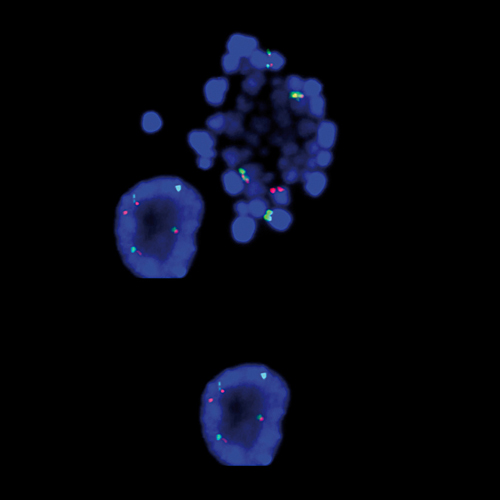

Hybridization of MYC TC break probe to a tissue section showing abarrant pattern (1GBR1G1BR).

IVD MYC (8q24) Break (tissue)

Rearrangements of the proto oncogene MYC c-myc) have been consistently found in Burkitt's lymphoma tumor cells. In cases with the common t(8;14) chromosomal translocation, the MYC gene is translocated to chromosome 14 and rearranged with the immunoglobulin heavy chain genes; the breakpoint occurs 5' to the MYC gene and may disrupt the gene itself. In Burkitt's lymphoma showing the variant t(2;8) or t(8;22) translocations, the genes coding for the k and l immunoglobulin light chain are translocated to v-myc avian myelocytomatosis viral oncogene homolog (MYC or c-myc) chromosome 8. The MYC (8q24) Break probe is optimized to detect rearrangements involving the 8q24 locus in a triple-color, split assay on formalin fixed paraffin embedded tissue.